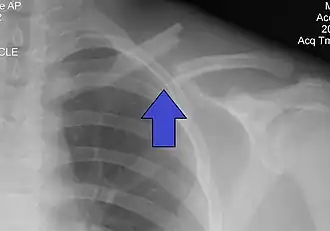

Перелом ключицы — патологическое состояние, проявляющееся нарушением анатомической целостности ключицы. Чаще всего переломы происходят в средней трети на границе наружной и средней третей ключицы, на наиболее изогнутой и истончённой её части. Наиболее часто встречающиеся — косые и оскольчатые.

Составляет 2,6-12 % от всего числа переломов, 44-66 % переломов плечевого пояса. В 80 % случаев перелом происходит в средней трети, 15% — перелом акромиального конца ключицы, 5 % — стернального (грудинного).

Переломы средней трети ключицы распространенная травма, составляющая от 2 до 5% всех переломов, от 35 до 45% повреждений верхних конечностей. Согласно результатам различных биомеханических исследований, средняя треть —наиболее слабое место ключицы, с чем связана высокая частота переломов этой локализации[1].

Локальная болезненность, припухлость, деформация, кровоизлияние и укорочение надплечья, плечо опущено и смещено кпереди. Периферический отломок вместе с верхней конечностью под влиянием её тяжести и сокращения большой грудной и подключичной мышцы смещается вниз, вперёд и внутрь. Центральный отломок под воздействием грудино-ключичной мышцы смещается кверху и сзади. Отломки сближаются и заходят один на другой.

Выполняется рентген в прямой и боковой проекциях.